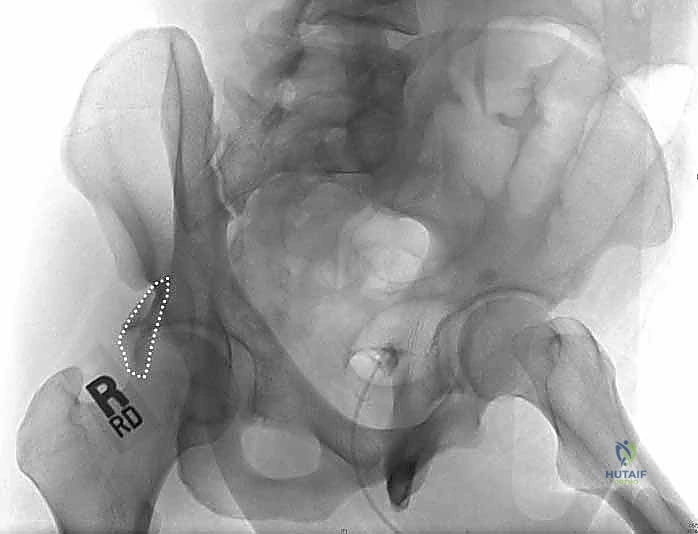

2. التصوير بالأشعة السينية (X-rays)

هي الخطوة الأولى. يتم أخذ صورة أمامية خلفية (AP) للحوض. ولكن في كسور الحُق، هذه الصورة لا تكفي. يتم طلب صور بوضعيات خاصة تُعرف بـ مناظر جوديت (Judet Views):

* المنظر المائل السدادي (Obturator Oblique): يوضح العمود الأمامي والجدار الخلفي.

* المنظر المائل الحرقفي (Iliac Oblique): يوضح العمود الخلفي والجدار الأمامي.

4. الرد التشريحي (Anatomical Reduction)

هنا تتجلى مهارة وخبرة الدكتور محمد هطيف. يقوم بجمع شظايا الجدار الخلفي المكسورة وإعادتها إلى مكانها التشريحي الأصلي بدقة المليمتر. يجب أن يكون السطح المفصلي أملساً تماماً لتجنب الاحتكاك. يتم استخدام أدوات خاصة، مثل الملاقط العظمية، للإمساك بالشظايا وتثبيتها مؤقتاً بأسلاك معدنية دقيقة (K-wires).